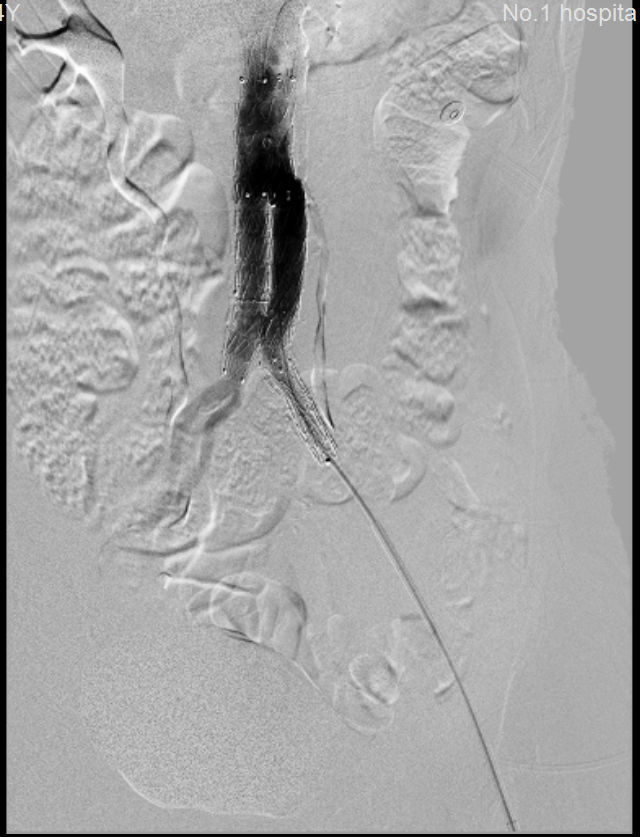

术前 术后